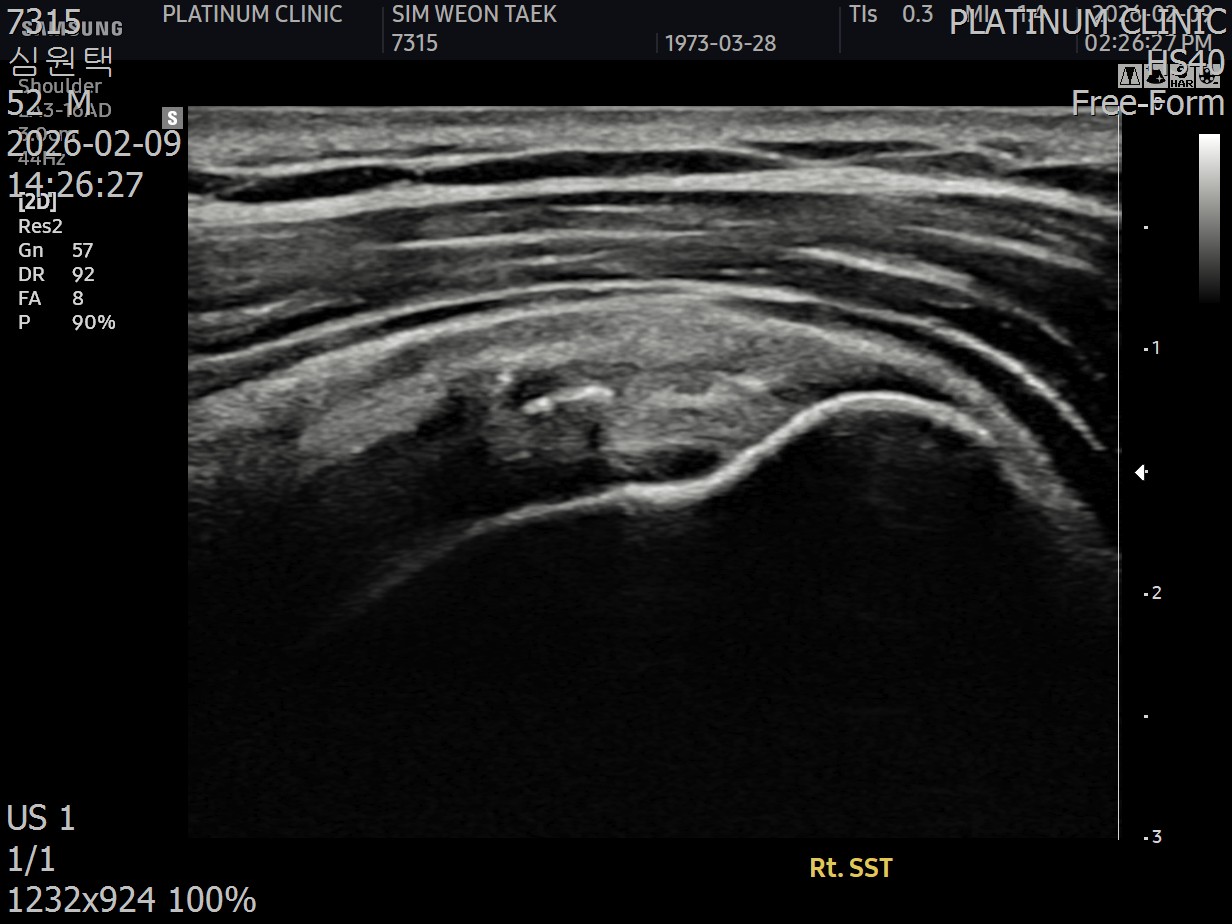

저는 이학적검사를 시행한 뒤, 초음파 검사를 진행했습니다. 그리고 발견했습니다.

회전근개 힘줄 사이사이에 미세한 석회 침착이 여러 군데 흩어져 있었습니다. 크기가 매우 작아서 3mm 단위로 단면을 촬영하는 MRI에서는 보이지 않았지만, 초음파로는 선명하게 확인되었습니다.

진짜 원인은 오십견이 아니라, 오십견을 유발하는 '석회'였습니다.